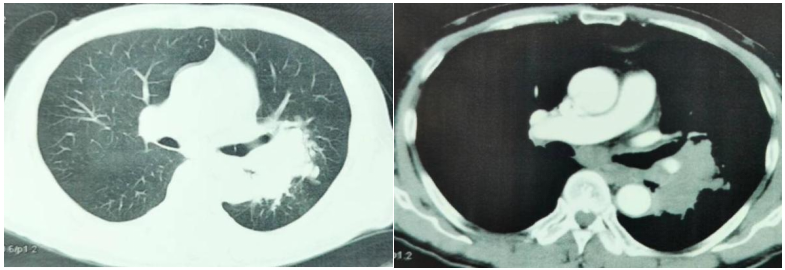

胸部增强CT(2022-05-17):考虑肿瘤性病变伴阻塞性炎症(左肺下叶背段支气管阻塞,肺门处见软组织团块影,呈分叶状,大小约9.8cm×4.6cm,包绕邻近血管);肿块旁多发小结节,子灶?左肺门及纵隔多发转移瘤。

图1.胸部增强CT

二线治疗第1周期后复查增强CT(2022-07-25):与2022-06-29CT对比:1.左肺上下叶肿瘤性病变(较大截面大小约5.9cm×4.5cm)伴阻塞性炎症,病灶较前缩小;肿块旁多发小结节,考虑转移灶,较前缩小;左肺门及纵隔多发转移瘤,较前缩小。2.右肺上叶及双肺下叶点状影,左肺下叶点状钙化灶。与2022-05-30CT对比:1.左侧肾上腺结节(较大者直径约1.0cm)考虑转移,病灶较前缩小。2.原片所示肝内转移灶本次检查显示欠清晰。

二线治疗第3周期后复查增强CT(2022-09-25):与2022-07-25CT对比:左肺上下叶肿瘤性病变伴阻塞性炎症(较大截面大小约5.1cm×3.2cm),肿块较前大致相仿,周围炎症较前略有吸收、减少;左肺门及纵隔多发淋巴结转移,部分较前略显缩小。与2022-07-25CT对比:1.左侧肾上腺肿块(最大横截面约3.4×2.1cm),较前增大,考虑肾上腺转移。2.肝右叶小囊肿可能。

图5.基线及治疗期间胸腹部CT